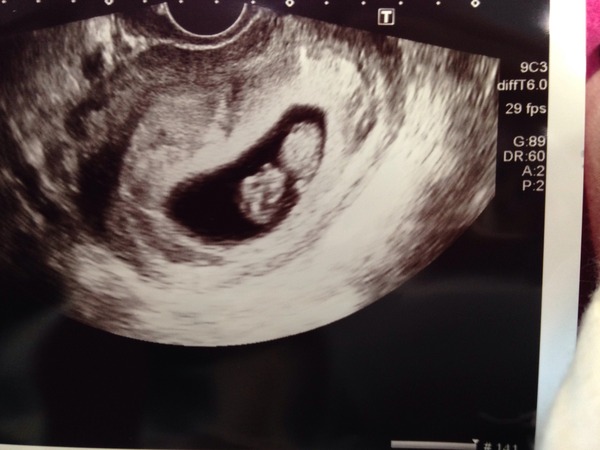

Ha ha re. grown up scan!! I've prepped myself for another tv scan at 12 weeks or whenever... Nope Keys still don't have an appt through, grr as my uterus is 180degrees retroverted and probably won't have moved up far enough by then (it's tucked behind my bowel!) Consultant had to press on my belly even with a tv scan!